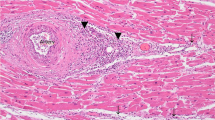

Microscopically, the heart demonstrated lymphocytic myocarditis. Myocardial fibers with conspicuous lymphocyte and plasma cell infiltration were found in cardiac tissue (Fig. 3a), consistent with the pathology of subacute myocarditis with early-stage fibrosis. The lung showed interstitial pneumonitis, and tissue presented with significant lymphocytic infiltration, especially around pulmonary vessels and bronchioles. There was no significant eosinophilic infiltration over the trachea. The hippocampus and medulla showed perivascular cuffing. The liver showed lymphocyte accumulation in the portal area, and there was microvascular fatty metamorphosis in the hepatocytes. The renal interstitium showed lymphocyte accumulation and germinal center formation. The white pulp and red pulp of spleen distributed evenly, and the red pulp was slightly congested. The adrenal medulla was congested with partial hemorrhage. There was tonsillitis with inflammatory cell infiltration in the epithelium. The mucosa of the colon showed lymphocyte accumulation and germinal center formation. The bone marrow demonstrated hemophagocytosis with many infected cells showing intranuclear inclusion bodies (Fig. 3b).

Case 2—a Myocarditis (× 100). Hematoxylin and eosin stain. b Many infected cells showed intranuclear inclusion bodies in the bone marrow (× 1000). Hematoxylin and eosin stain. c PVB19 was detected in macrophages by immunohistochemistry of myocardial tissue (× 400). d PVB19 was detected in bone marrow by in situ hybridization (× 200)

To determine a potential infectious etiology, screening was performed by MRT-PCR. The pathogens analyzed included herpesvirus type 1 to 8, influenza virus A and B, parainfluenza virus type 1 to 4, coronavirus, polyomavirus, chikungunya, dengue, West Nile virus, JE, adenovirus, rhinovirus, human metapneumovirus, respiratory syncytial virus, enterovirus, human parechovirus, human PVB19, bocavirus, Hendra virus, Nipah virus, mycoplasma, borrelia, Balamuthia, Acanthamoeba, Naegleria, and Toxoplasma (Table 1). In case 1, PVB19 was detected in bone marrow, heart, liver, spleen, lung, kidney, and basal ganglia (Table 2). In case 2, PVB19 was detected in trachea and throat swabs, as well as in fresh tissue of heart, lung, spleen, and liver and in blood specimens at a high viral load (Table 3). The bacterial isolation and virus isolation tests yielded no significant results. PVB19 was also detected in the myocardial tissue by immunohistochemistry in case 2. The positive signals were demonstrated in macrophages (Fig. 3c). Moreover, PVB19 was also detected in bone marrow by in situ hybridization in both cases (Figs. 2b and 3d).

PVB19-induced myocarditis has been reported since 1990 [12, 13]. Here, we report a case of an 11-month-old female infant with PVB19-induced fulminant lymphocytic myocarditis (case 2). It has been reported that PVB19 causes fatal myocarditis in immunocompetent adults [14,15,16], liver transplant recipients [17], and Brugada syndrome patients [18], but the most affected age groups of PVB19-associated fatal myocarditis are children (aged 3 to 11 years) [8, 9, 19,20,21,22,23], fetuses [24, 25], and infants [7]. Notably, the aforementioned reports demonstrated the relationship between myocarditis and PVB19 by indirect molecular and serology methods rather than by direct immunohistochemistry or in situ hybridization. This is precarious, because a recent study showed that the detection of PVB19 DNA was not sufficient for diagnosing myocarditis [26, 27]. Therefore, we used immunohistochemistry and in situ hybridization, in addition to microbiological examination, to confirm the pathogenesis of PVB19. The positive signals were demonstrated in macrophages by immunohistochemistry from myocardial tissue (Fig. 3c) and in red blood cell precursors by in situ hybridization from bone marrow (Fig. 3d).